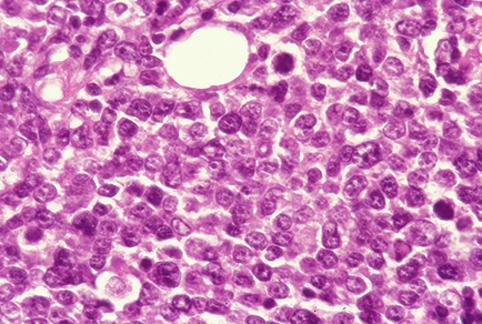

疾病(病理主体)的分类恶性淋巴系肿瘤/恶性淋巴瘤

部位(按器官分)胃(部位)/2个以上

检查方法病理切片(微观)

肿瘤最大直径40以上

肿瘤的深度sm